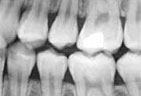

Digital X-rays

We use state of the art digital X-rays and digital cameras to help with an accurate diagnosis of any concerns. Digital X-rays use less radiation to get a diagnostic picture of your teeth and they help the environment by eliminating the use of chemicals to process the film.